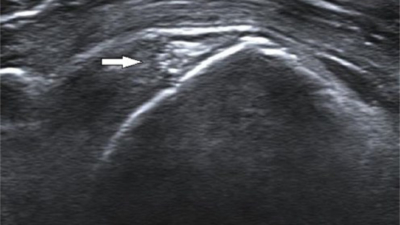

Op deze echo is boven de diffuse kalkafzetting ook een klein scheurtje in de pees zichtbaar. Dit komt regelmatig voor bij patiënten met kalk.